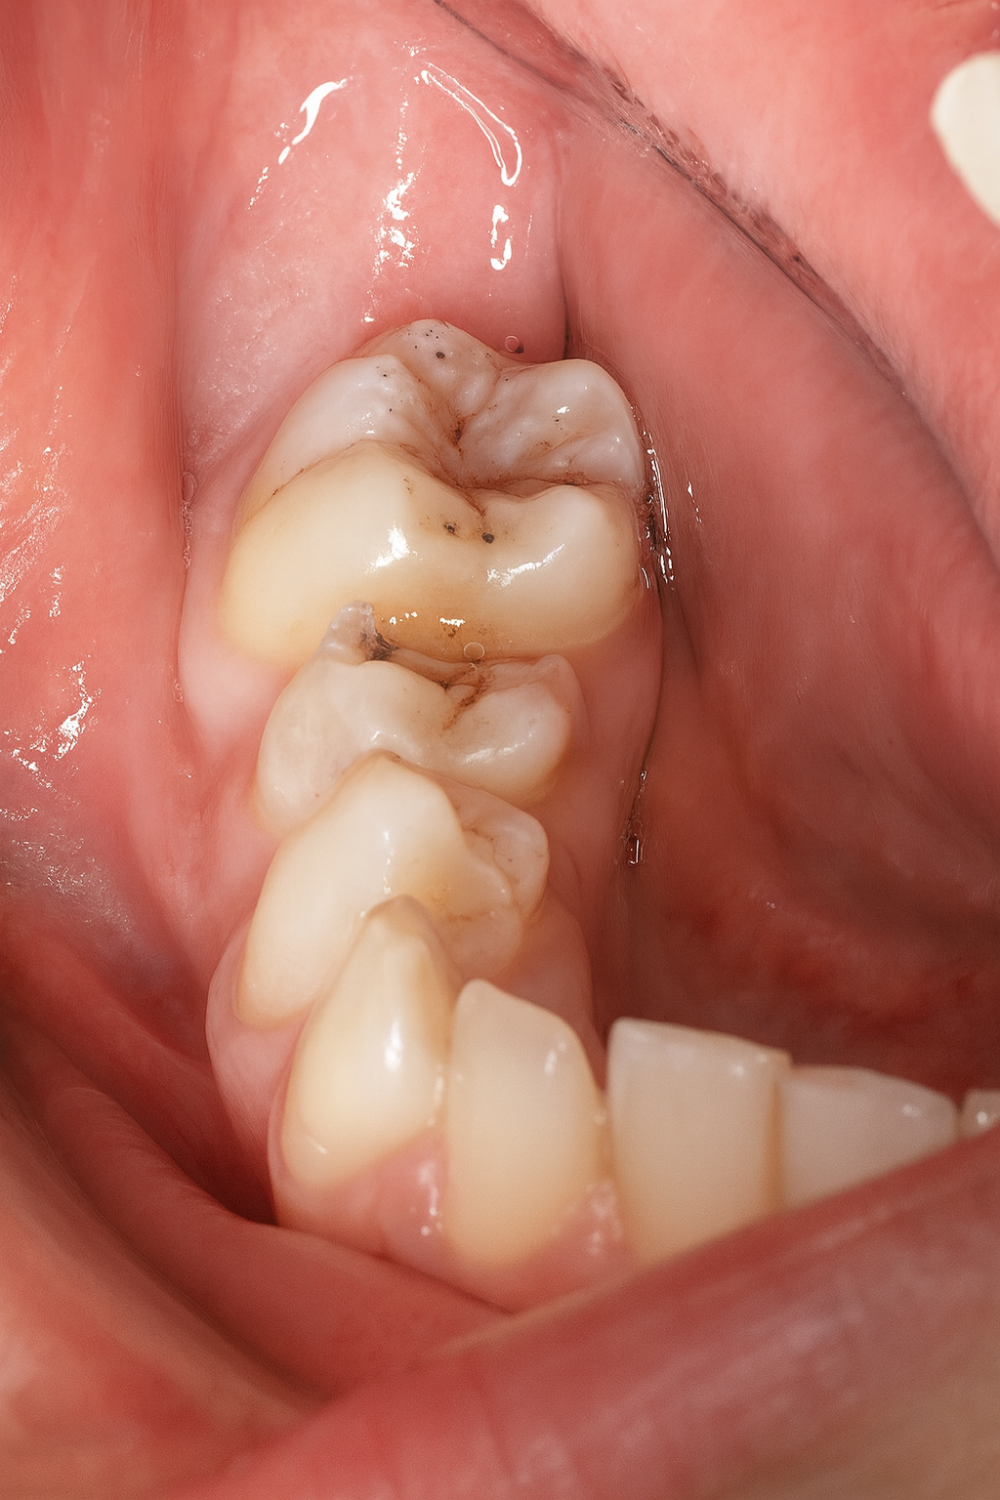

Métodos: Se presenta el caso clínico de un paciente varón de 18 años en el que, tras la realización de una CBCT de la arcada mandibular, se observó la retención de los segundos molares mandibulares permanentes junto con los terceros molares mandibulares.

Clínicamente la impactación de los 2M puede dar lugar a diversas complicaciones locales, entre las que se incluyen la aparición de lesiones quísticas, procesos infecciosos como la pericoronaritis o los abscesos, así como la sobreerupción de dientes antagonistas. Además, esta condición puede favorecer la aparición de patologías en los dientes adyacentes, tales como reabsorción radicular, caries, alteraciones periodontales, repercusiones estéticas y funcionales, incluyendo dificultades masticatorias7.

En relación con este último punto, autores como Shpack y cols.9 examinaron 165 segundos molares mandibulares impactados, observando que la mayoría (88%) presentaban una angulación mesial, un 8% una posición vertical y un 4% una angulación distal. Monaca y cols.1 reportaron que sólo 7 de los 161 molares impactados presentaban una angulación superior a 90°. De manera similar, Fu y cols.2 en su estudio, únicamente 5 de los 125 molares impactados mostraban una angulación mayor a 90°, siendo extremadamente rara la presentación horizontal de estos dientes.